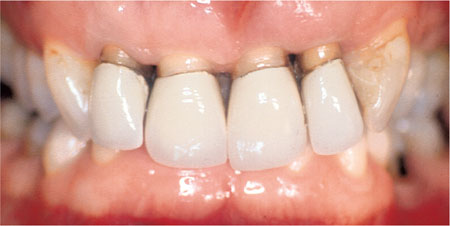

Indirect restorations can fail as a result of periodontal disease. This can occur as a consequence of poor primary prevention prior to the placement of restorations. Aggravating factors such as overhanging margins and overcontoured crowns can lead to secondary failure. The patient in Fig 1-8 illustrates both of these points. Failure to establish good periodontal health prior to preparing the upper incisor teeth for crowns led to further attachment loss and recession. This was exacerbated by deficient crown margins. Successful periodontal treatment led to resolution of inflammation, further recession and the need for crown replacement to improve the appearance of the teeth.

Fig 1-8 Gingival recession around upper incisor teeth following successful periodontal treatment subsequent to the placement of the crowns.